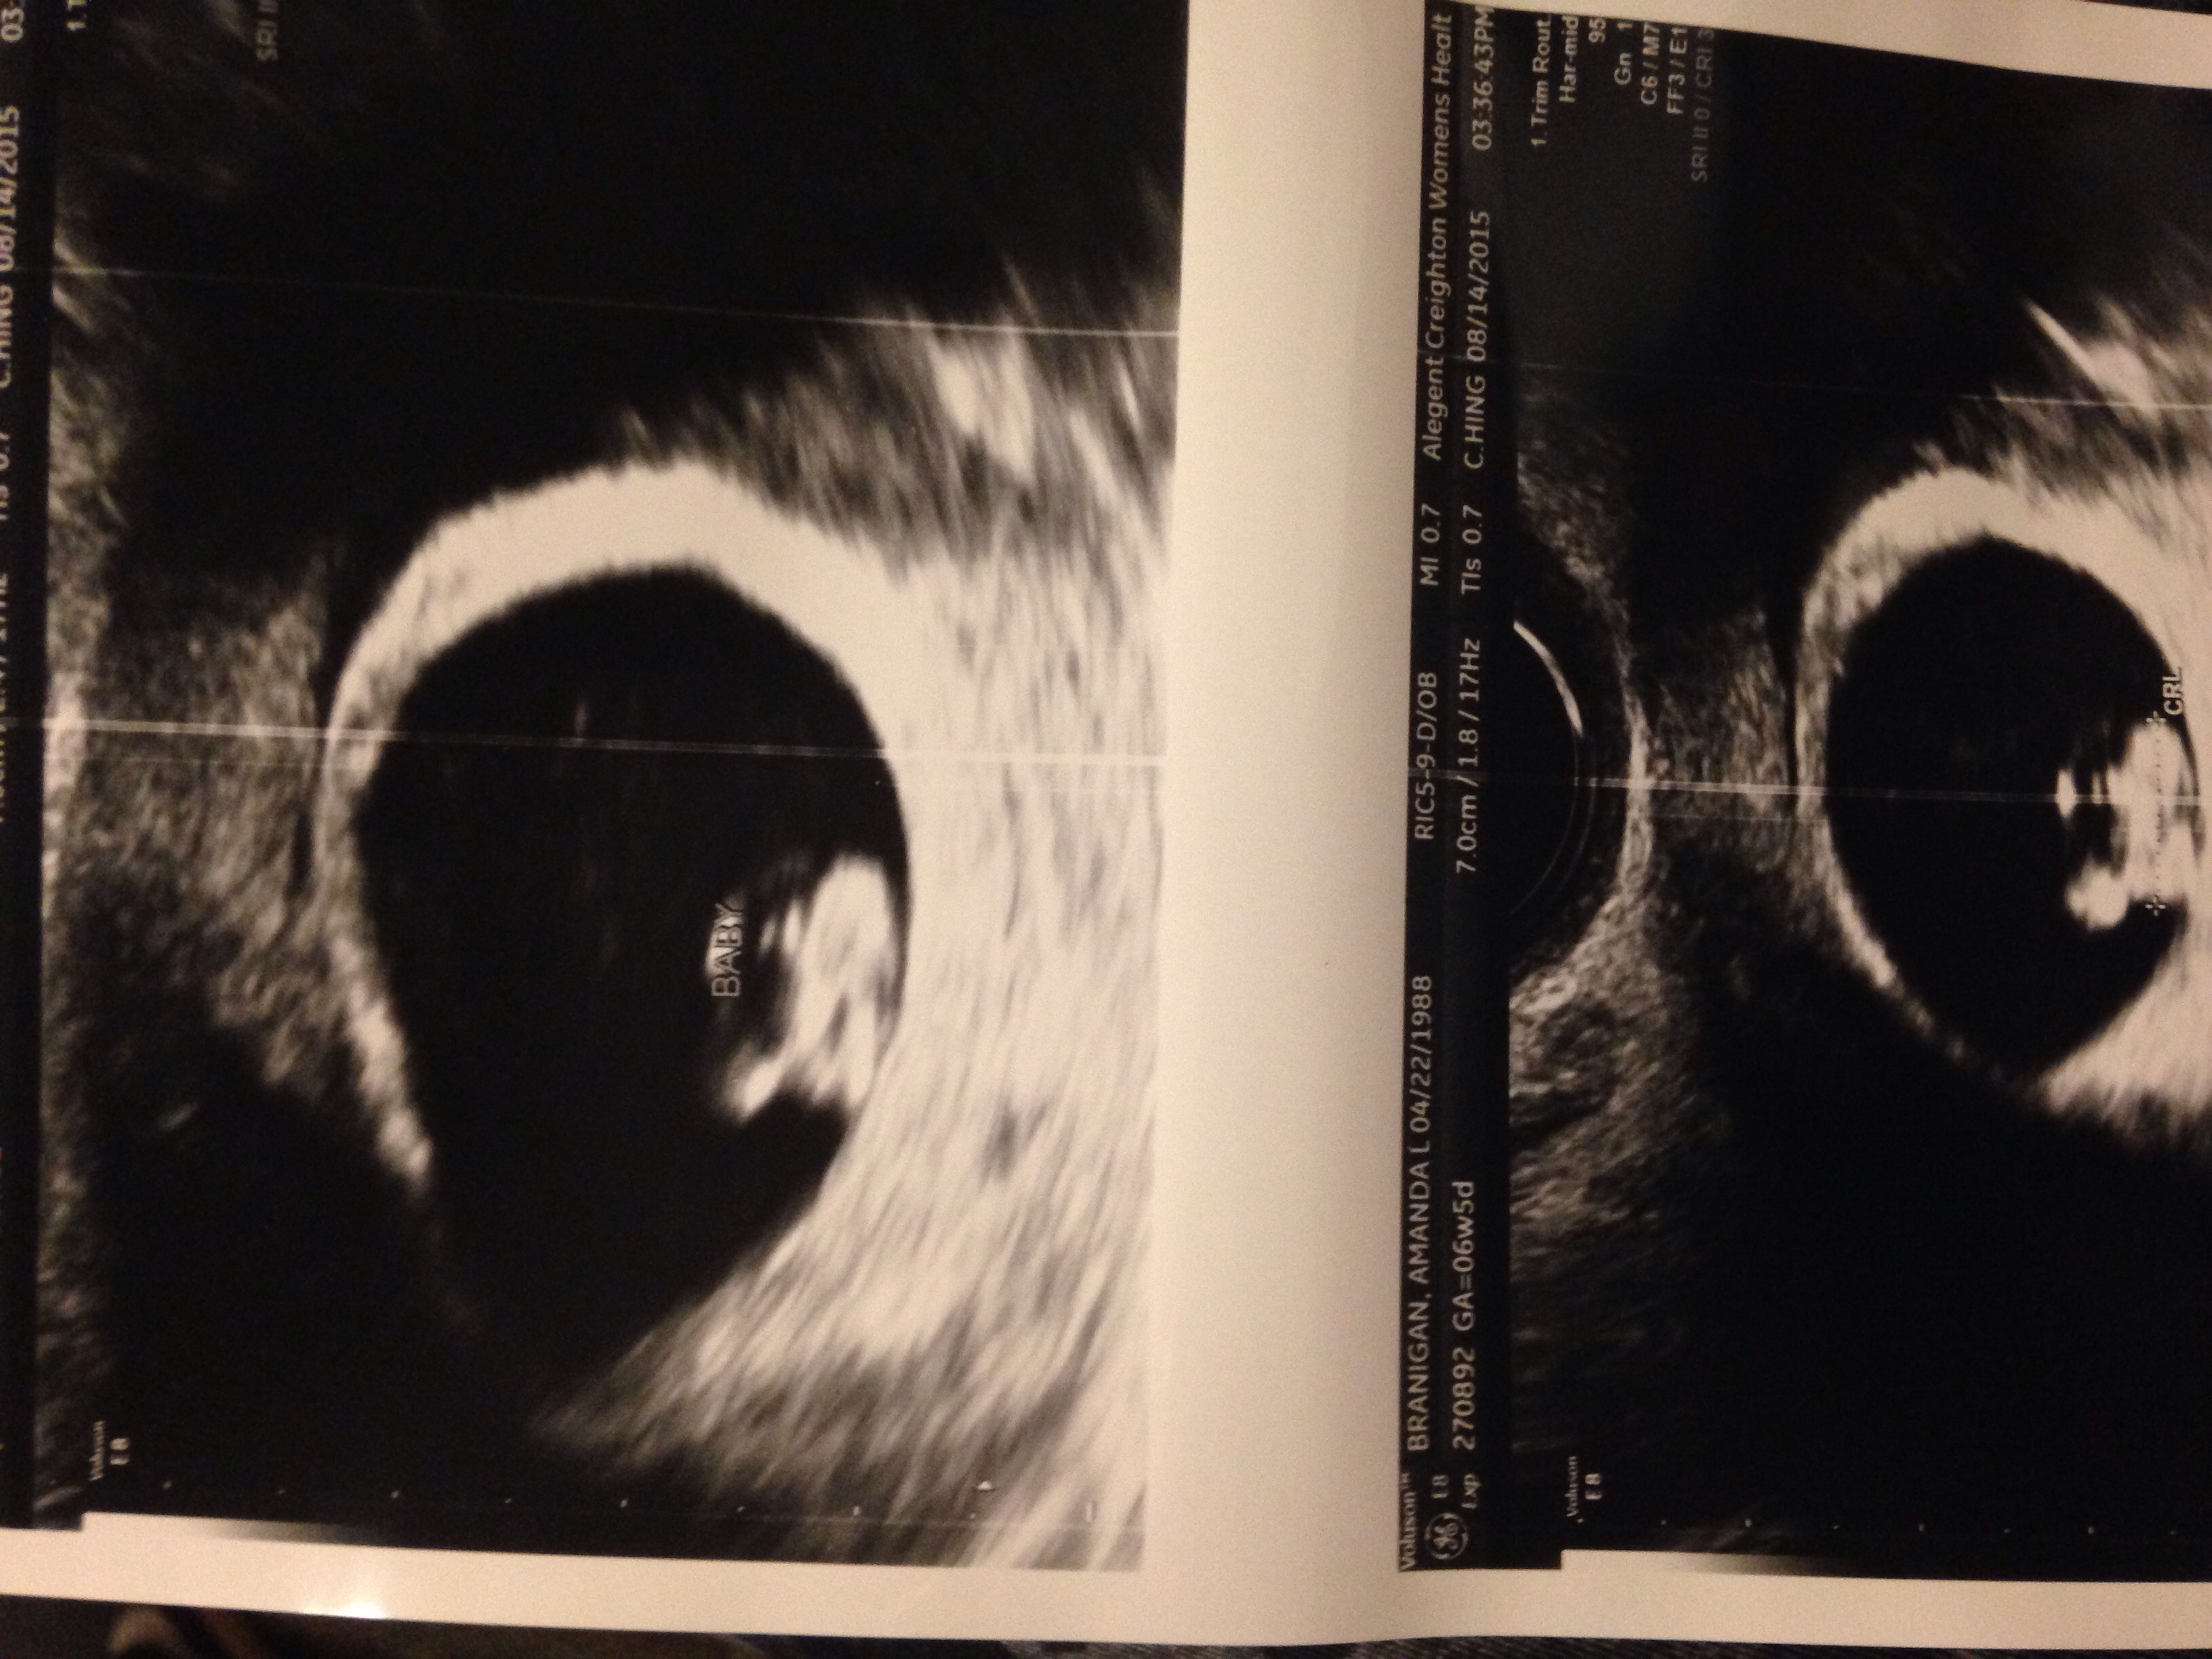

I am expecting twins. At 6w6day pregnant I had my u/s on 8/13 ( baby a measure at seven weeks and baby b 6w5days. Both of them doing great with strong hearts beats. So happy and exciting for all of us.